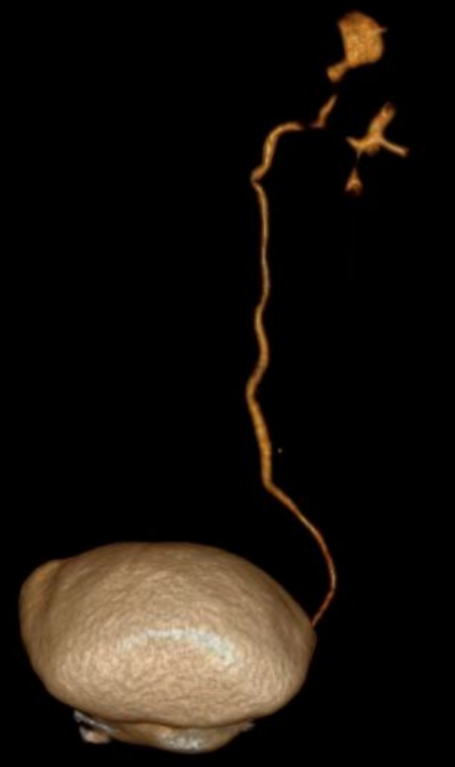

近日,我院泌尿外科团队成功为一位饱受多年右侧腰腹部疼痛困扰的67岁患者(化名:李阿姨),实施了高难度、高精度的腹腔镜下右肾切除术。手术过程顺利,患者恢复良好,术后第4天即康复出院。 李阿姨长期遭受右侧腰腹部的疼痛困扰。来院就诊后,泌尿外科蒋勇军主任详细询问病史得知,她曾因右侧肾结石接受过手术治疗。进一步的系统检查(包括下腹部CT平扫和CT尿路成像)揭示了问题根源:患者右侧肾脏存在严重肾积水,肾实质已极度萎缩、变薄,功能完全丧失。影像学显示,在排泄期长时间观察下,右肾已无显影,确认其功能完全丧失。 蒋主任分析认为,患者既往的结石病史可能导致输尿管狭窄或闭锁,引发了长期的尿路梗阻和肾积水,最终造成右肾不可逆的萎缩。而萎缩肾脏可能存在的炎症,正是其持续疼痛的原因。 面对患者切除无功能病肾的诉求,蒋勇军主任团队经过严谨评估,决定迎难而上,采用腹腔镜微创技术实施右肾切除术。该手术属于最高难度的四级手术,对医院综合实力和主刀医生的技术要求极高。手术面临两大挑战: 1、组织粘连重:萎缩的肾脏因继发炎症,与周围组织形成致密粘连,分离难度大。 2、血管处理难:萎缩肾脏的血管结构不清、纤细且被纤维组织包裹,解剖分离需极其精准,稍有不慎易损伤邻近重要血管和器官。 6月17日,手术如期进行。术中腹腔镜视野下,可见患者右肾萎缩呈“皮囊样”,肾实质薄如纸片,与周围组织粘连紧密,肾血管结构不清。蒋勇军主任团队凭借丰富的腹腔镜操作经验和精湛的解剖技巧,如同精雕细琢般,仔细分离粘连组织,精准处理纤细的肾血管及输尿管,最终完整、安全地切除了病变右肾。手术历时约3小时,顺利完成。 术后病理检查结果证实为“肾萎缩”,与术前诊断完全一致。在泌尿外科医护团队的精心治疗和护理下,李阿姨恢复迅速,疼痛解除,术后第4天即满意出院。出院前,蒋主任特别叮嘱她:务必保护好唯一的左肾,定期复查泌尿系统,发现异常及时就医处理。